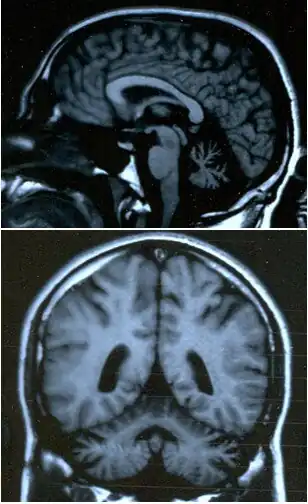

Ataxia (do grego ατάξις, sem coordenação), ou distaxia, é um transtorno neurológico caracterizado pela falta de coordenação de movimentos musculares voluntários e de equilíbrio. É normalmente associada a uma degeneração ou bloqueio de áreas específicas do cérebro e cerebelo.

O cerebelo é responsável por uma série de comandos centrais tendo papel de destaque na elaboração, aprendizagem e execução da motricidade. Os possíveis sintomas incluem: